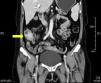

Presentamos el caso de una paciente de 58 años que acudió a consulta por dolor abdominal en el flanco derecho de 2 meses de evolución, cambios en los hábitos intestinales con estreñimiento y pérdida de peso de 5kg. A su ingreso, los signos vitales y los exámenes de laboratorio se encontraron dentro de los límites de normalidad. En la exploración física se detectó una masa en la fosa iliaca derecha y dolor leve a la palpación, sin datos de irritación peritoneal. En la colonoscopia, presentó una lesión estenosante en el ciego, se tomaron biopsias que revelaron únicamente inflamación crónica inespecífica. La tomografía abdominal mostró una tumoración a nivel del ciego de 5cm, con realce de la pared en el íleon terminal y en el ciego, además de adenopatías (fig. 1). Ante la sospecha clínica de neoplasia, la paciente fue sometida a hemicolectomía derecha laparoscópica. Como hallazgo transoperatorio, se reportaron adenomegalias peritumorales mayores de 1cm. Durante el examen macroscópico, se observó apéndice cecal de 5×1.5cm, con paredes engrosadas y obliteración fibroadiposa de la luz y lesión mal delimitada de aspecto abscecificado en el ciego. Durante el examen histopatológico se visualizó absceso pericecal con extensa colonización por Actinomyces spp., «gránulos de azufre» e inflamación aguda y crónica (fig. 2). Ante los hallazgos, se inició terapia con amoxicilina más ácido clavulánico durante 4 meses. La evolución postoperatoria de la paciente fue satisfactoria, siendo egresada al cuarto día postoperatorio. La actinomicosis es una enfermedad supurativa crónica que se manifiesta con la formación de fístula, seno, seudotumor inflamatorio o absceso. Son estas características las que obligan a considerar entre los diagnósticos diferenciales la enfermedad inflamatoria intestinal, la enfermedad pélvica inflamatoria y la tuberculosis. La infección puede simular malignidad por su capacidad de invadir los tejidos adyacentes y de formar masas4-6. Hasta el 80% de los casos ocurren en mujeres y el 60% se asocia a uso de dispositivo intrauterino2,4. La aparición de manifestaciones puede tomar de meses a años, pues los actinomicetos son organismos de crecimiento lento1,2. Los síntomas son inespecíficos y en la mayoría de los casos los estudios de laboratorio no demuestran anormalidades. Entre los hallazgos, se encuentran anemia normocrómica, leucocitosis y velocidad de sedimentación globular aumentada2,7. Al examen macroscópico del espécimen quirúrgico, se evidenció inflamación a nivel del apéndice. Actinomyces se encuentra de manera normal en zonas de estancamiento, como el ciego y el apéndice, los cuales son los órganos más frecuentemente involucrados en la localización abdominal1,4,5. El diagnóstico temprano y la antibioticoterapia oportuna de la apendicitis aguda reduce la incidencia de perforación, por lo que la inoculación a través de este proceso inflamatorio es rara. La diseminación es principalmente por continuidad de los tejidos y la vía hematógena o linfática es menos frecuente, por lo que la presencia de adenopatía regional no es común o se desarrolla tardíamente1,8. Las adenopatías peritumorales en el presente caso nos hicieron sospechar neoplasia como primera posibilidad diagnóstica. La presentación de actinomicosis como masa colónica indicativa de malignidad es infrecuente (1%)4. En la colonoscopia puede encontrarse edema y ulceración de la mucosa, nódulos umbilicados en el ápex y estenosis en algunos casos. La tomografía contrastada muestra frecuentemente involucro extramural y engrosamiento focal de la pared colónica9. El diagnóstico a través de biopsias por endoscopia o aspiración con aguja fina es complejo, pues los filamentos de Actinomyces se rodean de inflamación extensa5. Aunque el diagnóstico preoperatorio es útil para evitar una resección amplia, hasta en el 96% se requiere diagnóstico quirúrgico. El manejo quirúrgico permite retirar el tejido necrótico, la corrección de fístulas y acortar la duración del tratamiento antimicrobiano3,4,10. La colonoscopía y la tomografía tienen un papel más importante en el seguimiento terapéutico. En el examen histopatológico, se observan «gránulos de azufre», los cuales reaccionan a las tinciones de Schiff y Grocott. El cultivo es complejo y puede ser negativo hasta en el 76%5. La identificación de las especies de Actinomyces es difícil y en nuestro caso no se pudo reconocer el agente específico. Sin embargo, son susceptibles a aminopenicilinas y la combinación con inhibidores de la β-lactamasa debe ser considerada como la terapia de primera línea. Después de 4 meses de tratamiento, no se encuentran recidivas de la enfermedad10.